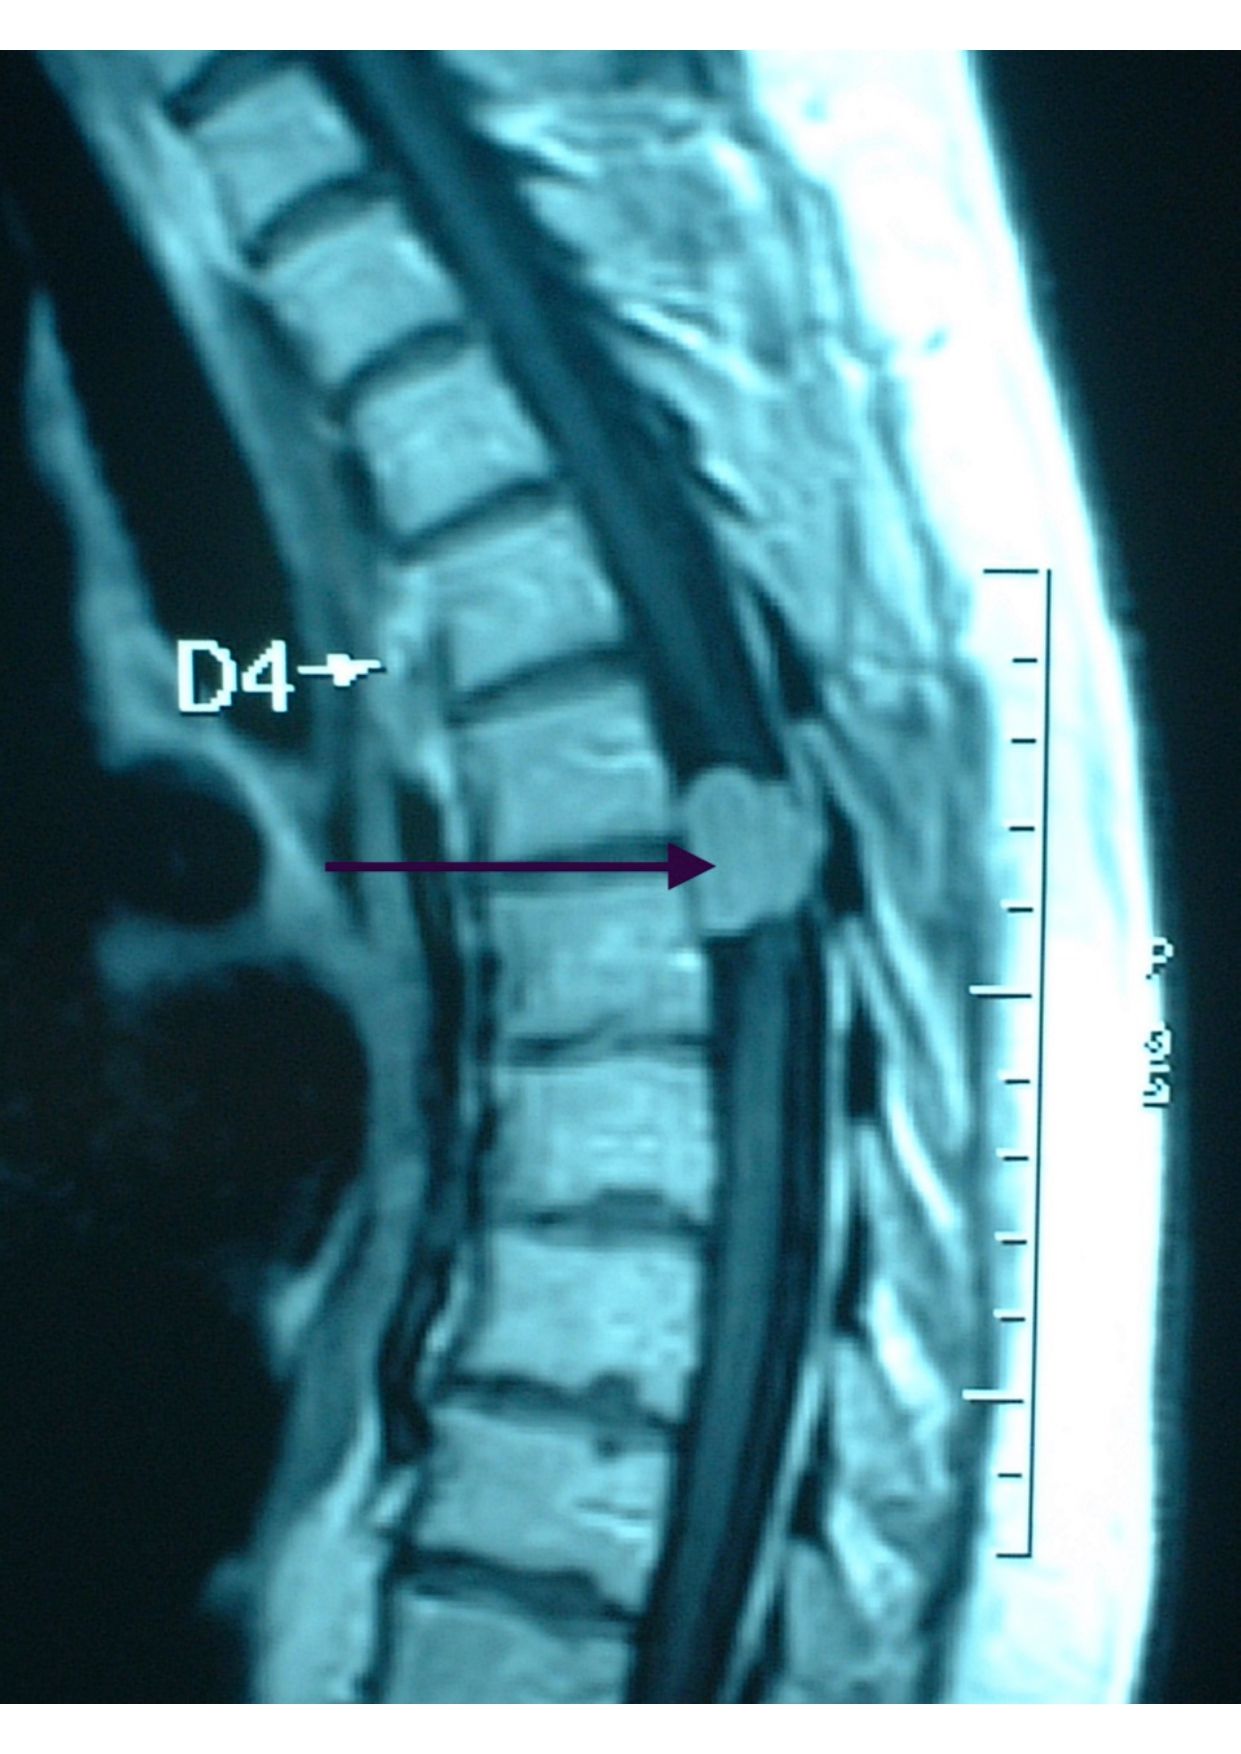

Patologias Tumoral Crânio Encefálica e Raquidiana

- Diagnóstico e tratamento de tumores que afetam o cérebro e a coluna vertebral.

Patologia Degenerativa da Coluna Vertebral

- Tratamento de doenças que afetam a estrutura e função da coluna, com potencial impacto na qualidade de vida.

- Hérnia discal